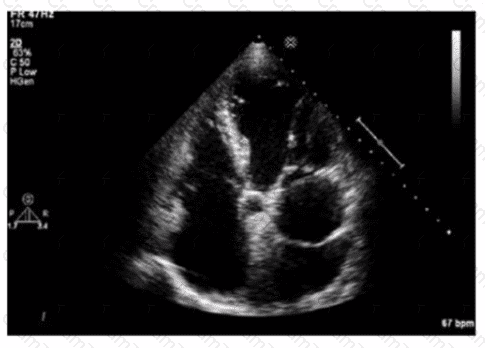

What is the incidental finding seen by color Doppler in this four-chamber view of a patient with left atrial enlargement?

Which diagnosis is most likely confirmed by echocardiography in a 65-year-old female presenting with new onset chest pain associated with ST segment elevation on the electrocardiogram and angiographically normal coronary artenes?